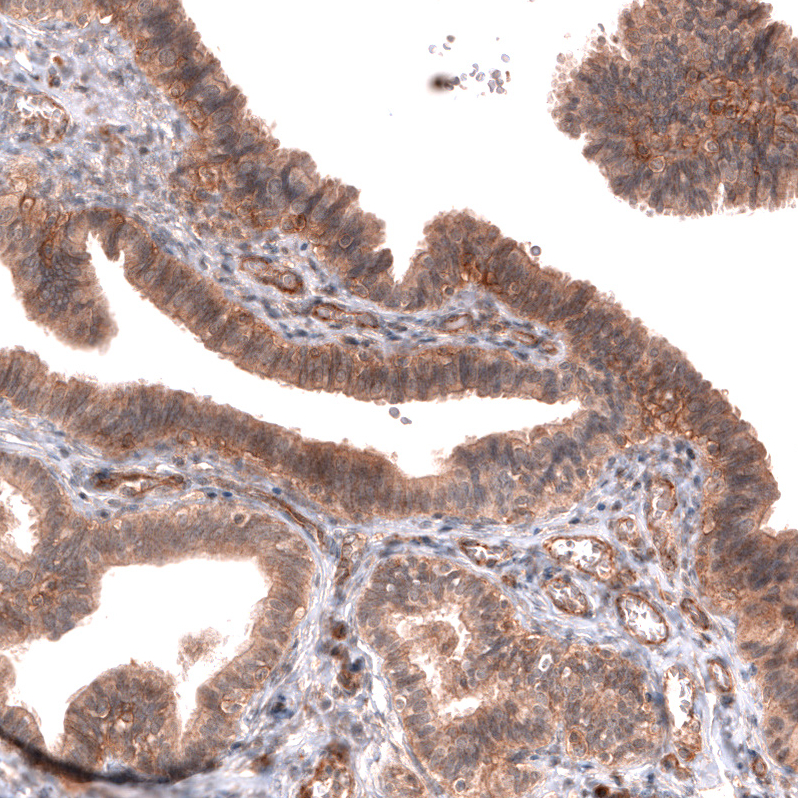

Immunohistochemical staining of human ovarian cancer (high grade serous carcinoma) shows strong membranous positivity in tumor cells.